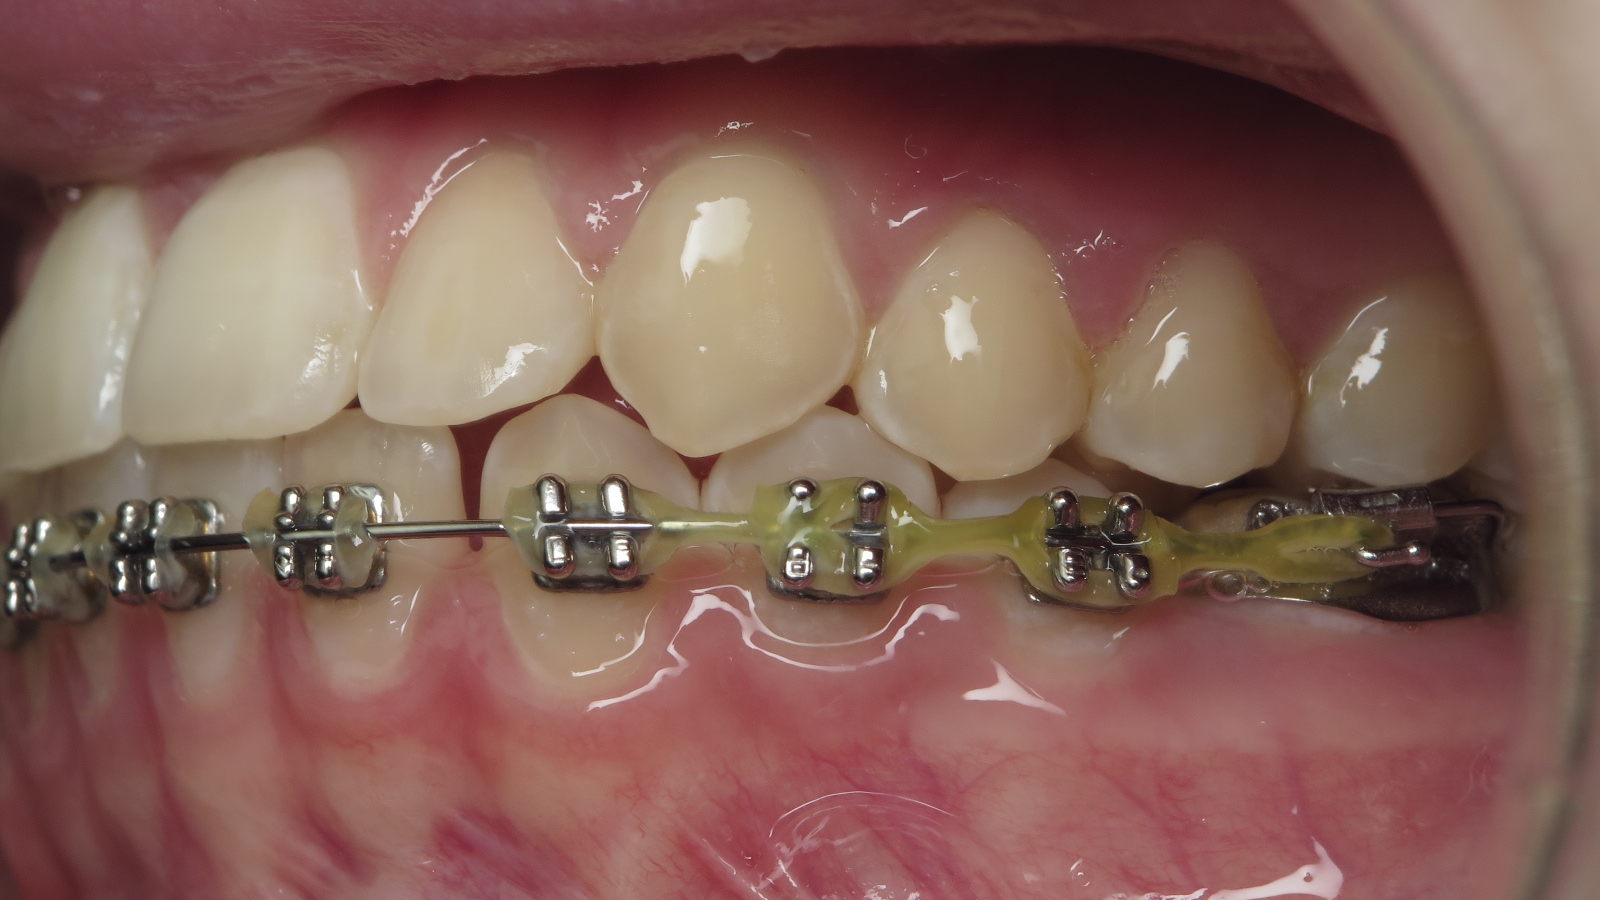

appareillage multibagues traitement en cours

bilan début et en cours de traitement